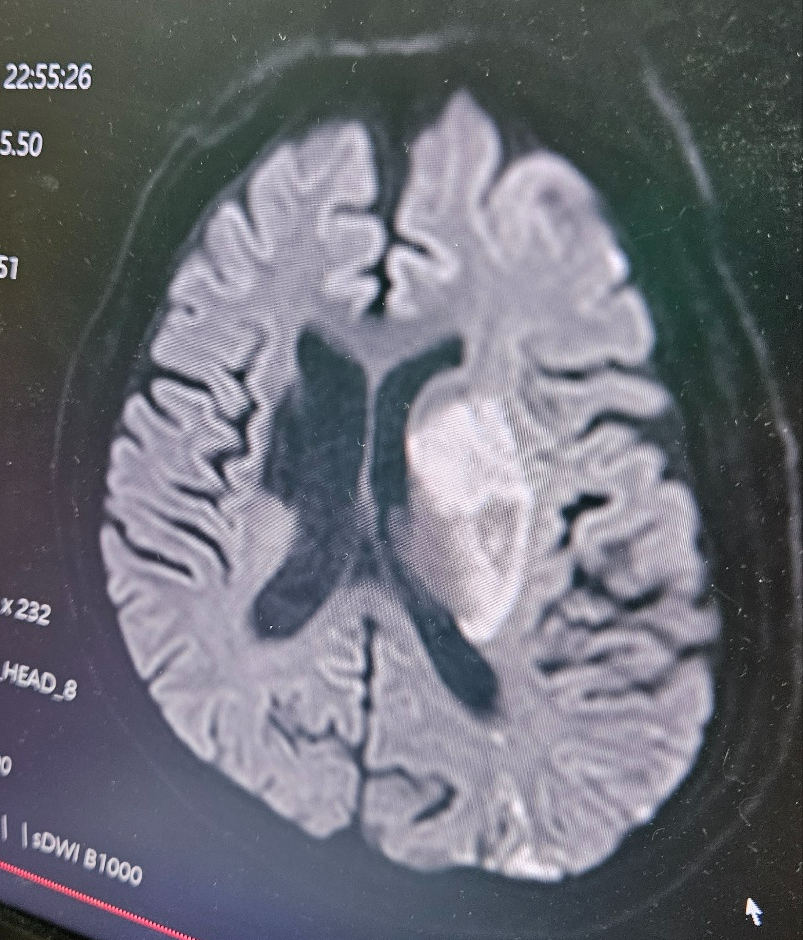

응급실에서 뇌 사진을 보여줬다. 가족들에게 설명을 해야되기에 사진촬영해도 되냐고 물었고, 허락을 받고 사진 촬영을 했다. 가운데 하얀 부분이 뇌경색이 온 부분이란다. 한눈에 봐도 이건 큰일이구나 싶었다. 뇌혈관 MRI도 일반인의 사진은 밤에 불이 켜져있는 도시처럼 밝게 느껴졌는데 아빠의 사진은 점점 어두워지고 있는게 느껴졌다. 그렇게 꼬박 하루를 응급실에서 밤을 새고 출근도 못한 채 언니와 교대를 하고 비몽사몽 이게 무슨일인지 무슨일이 벌어지고 있는건지 생각할 새도 없이 응급실에서만 그 하루 87만원정도의 돈이 나왔다.